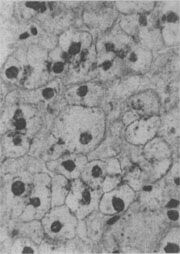

图1-18 肝细胞脂肪变性 肝细胞胞浆内出现大小不等的脂肪空泡;右上角为饿酸染色的脂肪细胞, 脂滴染成黑色 (2)心肌脂肪变性:心肌在正常情况下可含有少数脂滴,脂肪变性时脂滴明显增多。镜下,脂肪空泡较细小,呈串珠状成排排列,主要位于肌纤维Z带附近和线粒体分布区。常为贫血和中毒的结果。在严重贫血时,可见心膜下尤其是乳头肌处出现成排的黄色条纹,与正常心肌的暗红色相间排列,状若虎皮斑纹,故有“虎斑心”之称。严重感染、白喉外毒素以及其他毒物(如磷、砷、氯仿等)也能引起心肌的弥漫性脂肪变。肉眼观,心肌均匀变浊,略呈黄白色。但通常心功能并不受明显影响。显著的心肌脂肪变性如今并不常见。 (3)肾脂肪变性;在严重贫血、缺氧和中毒过程中,或肾小球毛细血管通透性升高时,肾小管特别是近曲小管的上皮细胞可吸收漏出的脂蛋白而导致脂肪变性。脂滴起初多位于细胞基底部。肉眼观,肾稍肿大,切面上可见皮质增厚,略呈浅黄色。 2.玻璃样变性 又称透明变性(hyaline degeneration),为十分常见的变性,主要见于结缔组织、血管壁,有时也可见于细胞内。 1.结缔组织玻璃样变:常见于纤维瘢痕组织、纤维化的肾小球,以及动脉粥样硬化的纤维性瘢块等。此时纤维细胞明显变少,胶原纤维增粗并互相融合成为梁状、带状或片状的半透明均质,失去纤维性结构(图1-19)。质地坚韧,缺乏弹性。玻璃样变的发生机制尚不甚清楚,有人认为在纤维瘢痕老化过程中,原胶原蛋白分子的交联增多,胶原原纤维也互相融合,其间并有较多的糖蛋白积聚,形成所谓玻璃样物质;也有人认为可能由于缺氧、炎症等原因,造成局部pH升高或温度升高,致使原胶原蛋白分子变性成明胶并互相融合所致。 2.血管壁玻璃样变:这种改变常见于高血压病时的肾、脑、脾及视网膜的细动脉。此时,可能是由于细动脉的持续性痉挛,使内膜通透性增高,血浆蛋白得以渗入内膜,在内皮细胞下凝固成无结构的均匀红染物质。此外,内膜下的基底膜样物质增多。这些改变使细动脉的管壁增厚、变硬,管腔变狭,甚至闭塞(图1-20),此即细动脉硬化症(arteri-olosclerosis),可引起肾及脑的缺血。 3.细胞内玻璃样变:亦称为细胞内玻璃样小滴变性。这种情况常见于肾小球肾炎或其他疾病而伴有明显蛋白尿时。此时肾近曲小管上皮细胞胞浆内可出现许多大小不等的圆形红染小滴(图1-21),这是血浆蛋白经肾小球滤出而又被肾小管上皮细胞吞饮的结果,并在胞浆内融合成玻璃样小滴,以后可被溶酶体所消化。此外,在酒精中毒时,肝细胞核周胞浆内亦可出现不甚规则的红染玻璃样物质。电镜下,这种物质由密集的细丝构成,据认为可能是细胞骨架中含角蛋白成分改变的结果,并被称为Mallory小体。